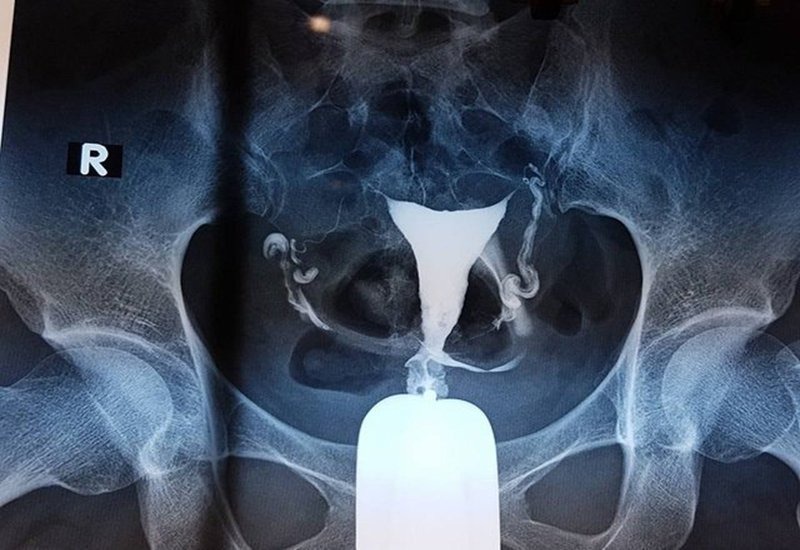

Dị vật trong bàng quang có thể xảy ra do tai biến hoặc sự vô tình của bác sĩ. Đó có thể là những dụng cụ y tế như chỉ phẫu thuật còn sót lại, mảnh vỡ bóng Foley hay còn gọi là bóng cố định ống thông tiểu, giá đỡ niệu quản quá hạn bị bỏ quên, dụng cụ nong niệu đạo, vòng tránh thai, đinh bấm trong phẫu thuật. Nguyên nhân thường là do bác sĩ không hướng dẫn rõ ràng cho bệnh nhân hoặc bệnh nhân quên tái khám để theo dõi.

Những người có tỷ lệ dị vật trong bàng quang cao nhất là những người có tiền sử phẫu thuật hệ tiết niệu hoặc các cơ quan lân cận như phẫu thuật sỏi thận, sỏi niệu quản, bướu tử cung… Ngoài ra, việc xuất hiện dị vật trong bàng quang còn do chính người bệnh gây ra, trường hợp này là do người bị rối loạn tâm thần như tâm thần phân liệt, hoang tưởng tự hại…, tự nhét dị vật vào cơ thể.

Do niệu đạo nam dài và có nhiều đoạn giải phẫu hơn nên vật lạ thường bị mắc kẹt trong niệu đạo hoặc bàng quang. Dị vật có thể là tóc, ống thông tiểu hay các sinh vật ngoại lai như đỉa, vắt…